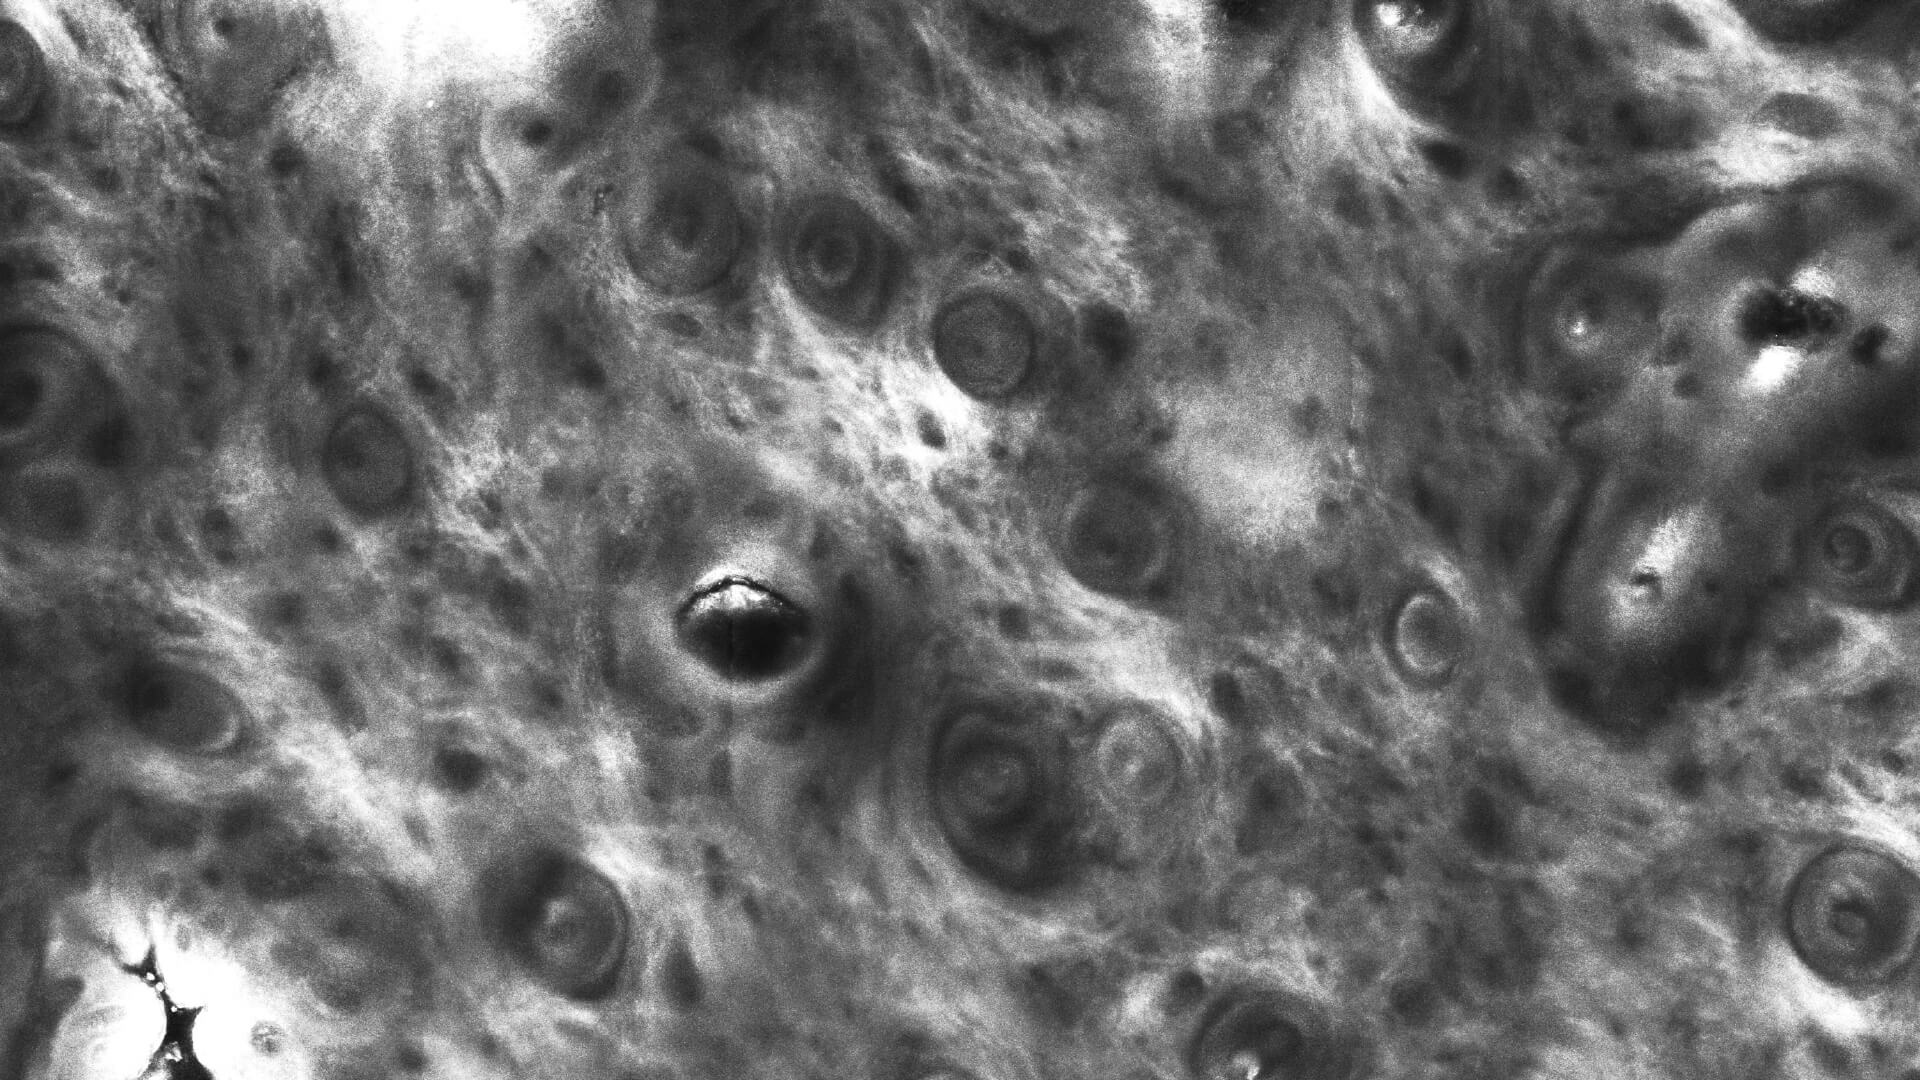

Our In Vivo product line allows for a real-time and non-invasive Instant Optical Biopsy from the epidermis to the upper dermis. With the VivaScope confocal laser scanning microscopy the cell morphology of the skin layers are displayed in high resolution.